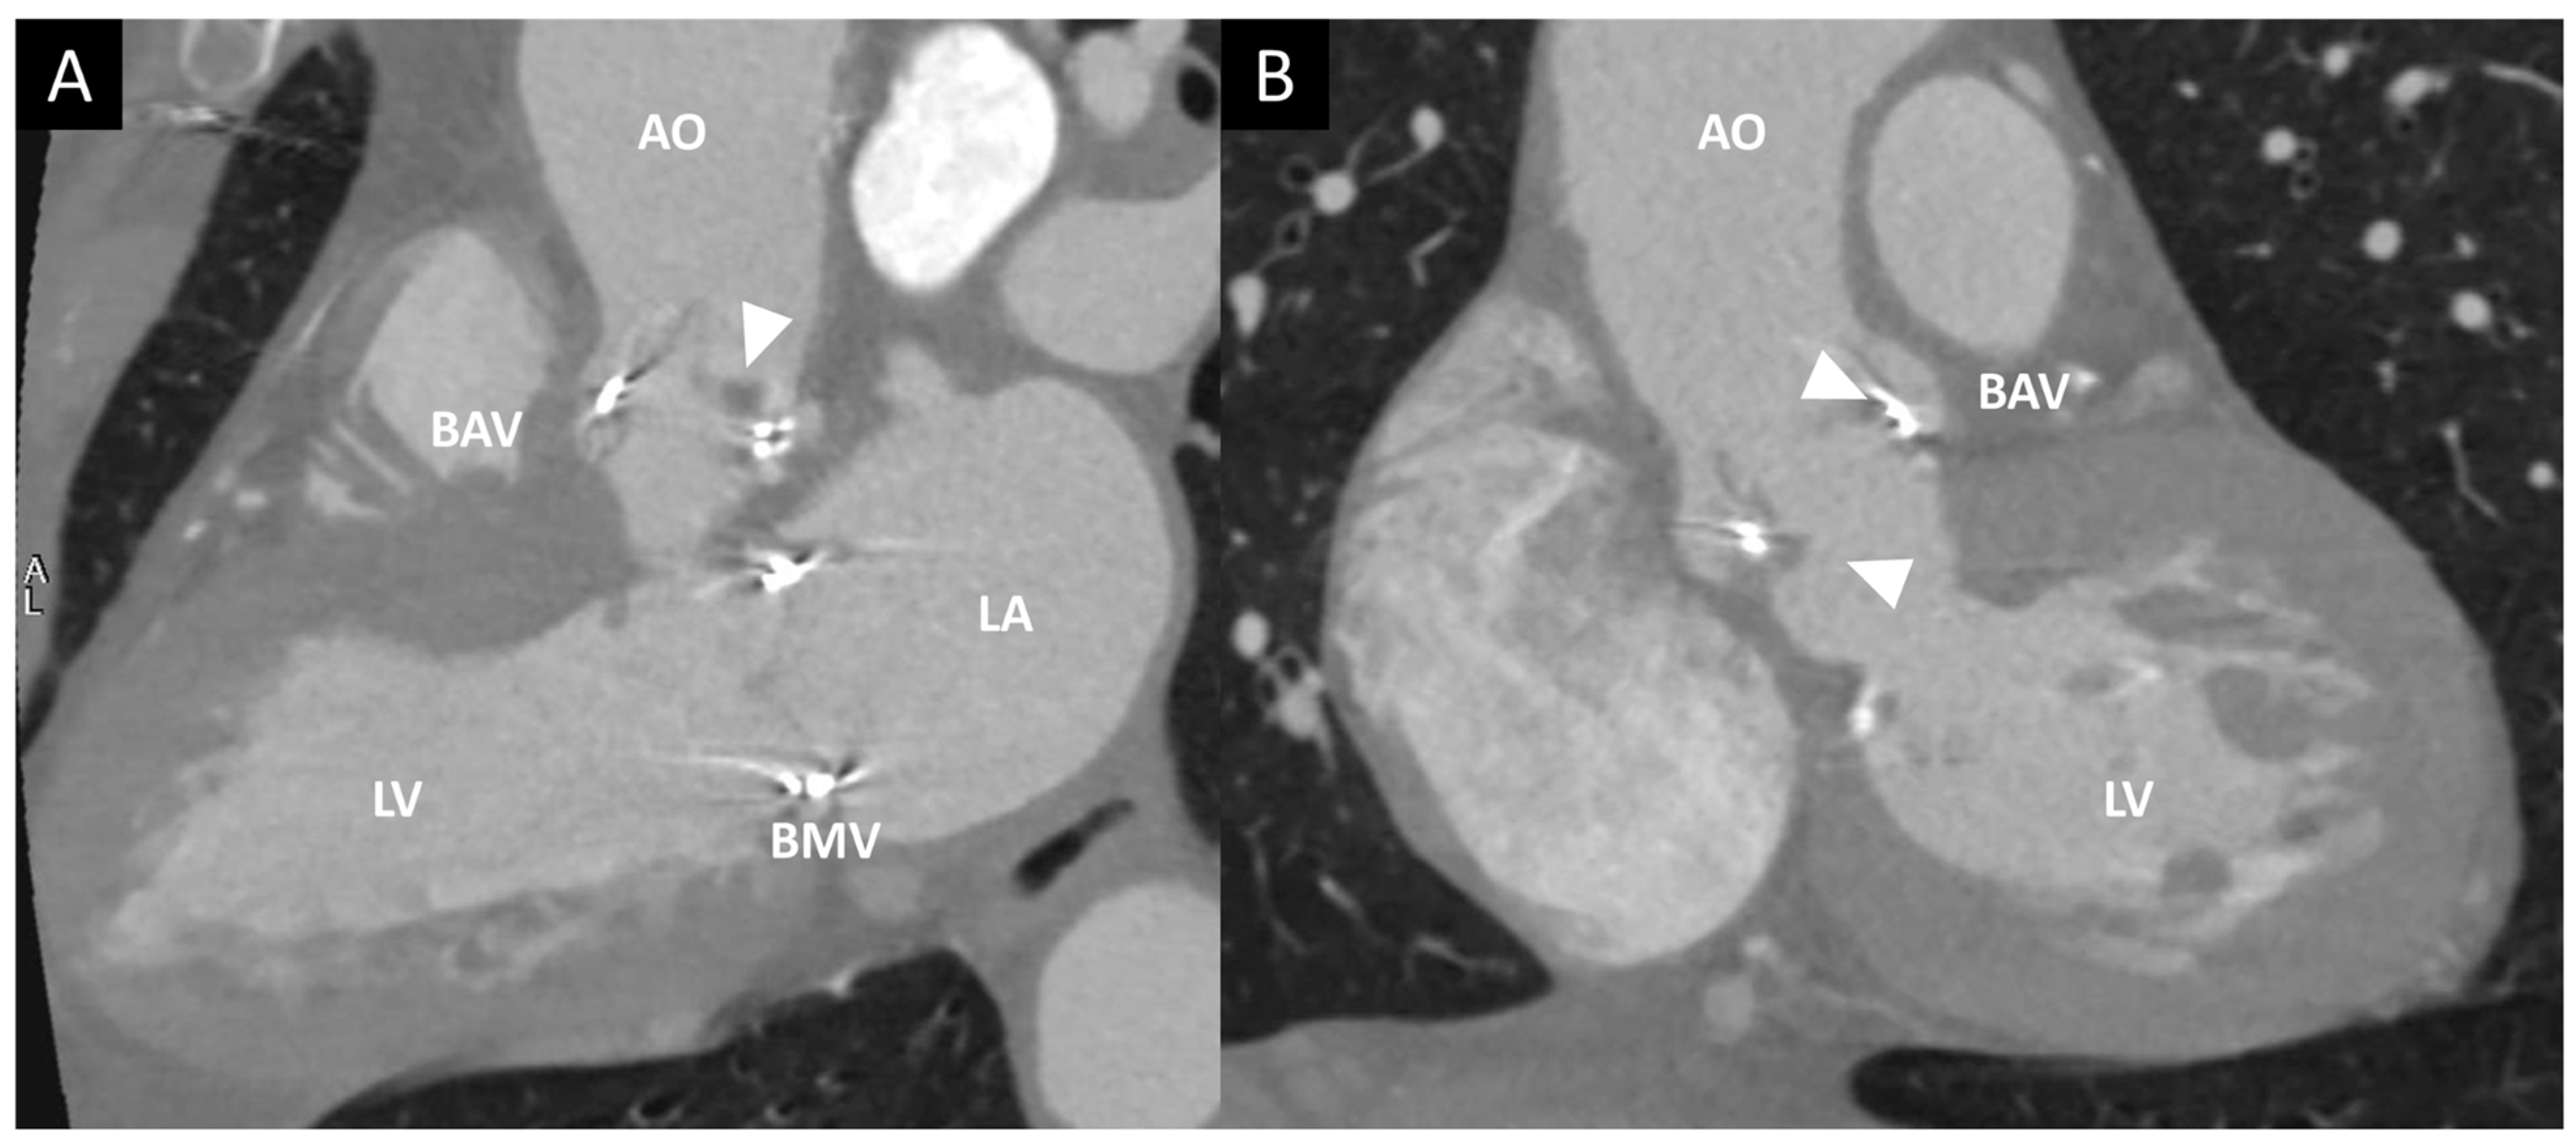

| TTE, TEE | Leaflet and/or ring thickening with diffuse or focal hyperechogenicity (calcifications). Reduced leaflet mobility. Leaflets’ fenestration, avulsion, or perforation. Stenosis or regurgitation. | Iso-hypoechogenic mass adherent to leaflets and ring, with leaflet thickening. Normal or reduced cusp mobility. More often, stenosis; regurgitation is uncommon. | Vegetations, diffuse or focal leaflets thickening, cusps perforation, wear or tear or cusp avulsion. Vegetation motion independent to cusps motion. Paravalvular complications: abscess, pseudo-aneurysm, fistula or dehiscence (and in some cases valve rocking) |

| CCT | Pannus (hypodense): HU ≥ 145; semicircular or circular structure located along leaflets’ surface or stent. Hyperdense leaflet thickening with or without calcifications, along with or without reduced mobility. | No calcifications. HU < 145. Hypoattenuated leaflet thickening (HALT), affecting (HAM) or reducing (RLM) leaflet motion. In some cases, large hypoattenuated mass. | Hypoattenuated mass adherent to leaflets or stent. Paravalvular complications: abscess, pseudo-aneurysm, fistula, or dehiscence. |